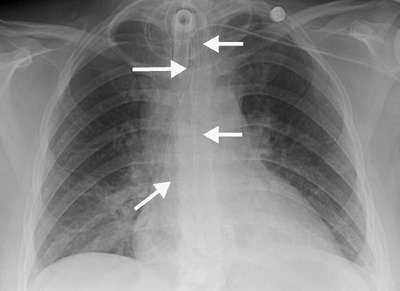

Chest Tubes

Pleural drainage tubes are used for evacuation of pleural fluid and air (hydrothorax and pneumothorax, respectively). Several types and sizes of tubes are used, and all should be evaluated by chest radiography for proper placement of the tip and side holes. A side hole is marked by an interruption of the radiopaque identification line; it should be medial to the inner margin of the ribs (Fig. 5-27). Placement of the tube tip in the

P.75

subcutaneous tissues, a fissure, or the lung parenchyma can be diagnosed with chest radiography or CT scanning. CT scans can also be used to identify loculated pleural collections and direct the placement of drainage tubes. Location within a fissure can be suspected when the tube reproduces the anatomy of the minor or major fissure, or when the tube takes more of a horizontal rather than a vertical course as seen on a frontal chest radiograph. Tubes within fissures may become occluded by the surrounding lung. Tubes can be inadvertently advanced into the mediastinum or through the lung parenchyma, liver, spleen, or diaphragm, resulting in bronchopleural fistula, hemorrhage, and infection (20,30). After removal of a thoracostomy tube, a residual pleural or parenchymal line from the tube track is often identified on the chest radiograph (Fig. 5-28); this should not be mistaken for the visceral pleural edge of a pneumothorax. If a large amount of pleural fluid is removed at one time (e.g., >1.5 L), rapid lung re-expansion can, rarely, result in so-called "re-expansion" pulmonary edema.